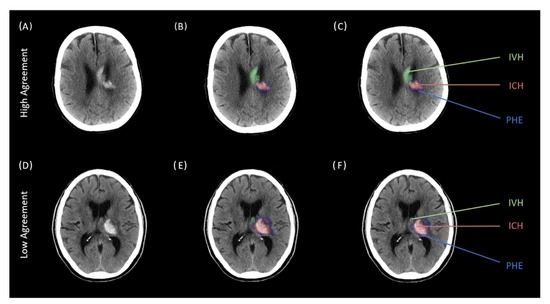

| Intraclass Correlation | ||||

|---|---|---|---|---|

| Region | ICC * | 95% Lower CI | 95% Upper CI | p-Value |

| ICH (n = 100) | 0.997 | 0.996 | 0.998 | <0.001 |

| PHE (n = 100) | 0.980 | 0.971 | 0.987 | <0.001 |

| IVH (n = 100) | 0.995 | 0.992 | 0.996 | <0.001 |

| Interclass Correlation | ||||

| ICH (n = 100) | 0.998 | 0.993 | 0.997 | <0.001 |

| PHE (n = 100) | 0.886 | 0.760 | 0.938 | <0.001 |

| IVH (n = 100) | 0.979 | 0.984 | 0.993 | <0.001 |